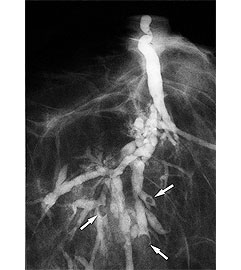

Галактографія – це рентгенологічний метод оцінки прохідності протоків молочної залози. За допомогою ділятаторів розширюють протоки молочної залози до потрібної ширини, а потім через голку вводять до протоків рентгеноконтрастну речовину. Після цього вивчають розподіл контрасту за допомогою рентген приладів.